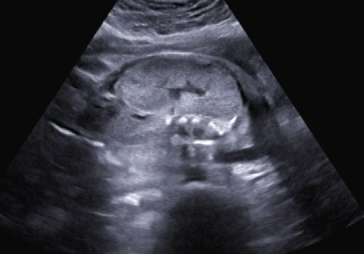

Ein zunächst durchgeführtes CTG war unauffällig. Im Rahmen der sonografischen Untersuchung zeigte sich der Fötus soweit beurteilbar zeitgerecht entwickelt. Dennoch konnte ein Anhydramnion festgestellt werden(Abb. 1, 2), weshalb auch kein fetales Gesicht darstellbar war (Abb. 3).